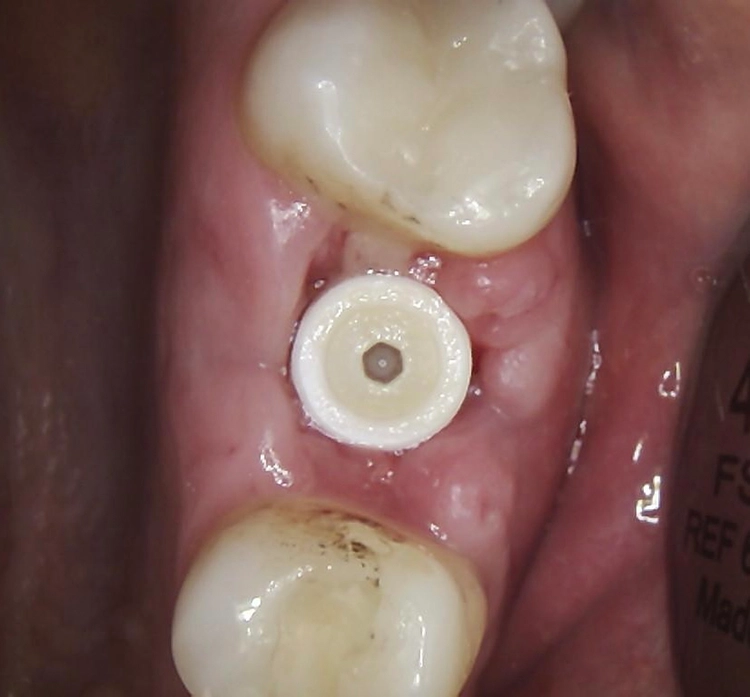

Bei dem balkonförmigen Implantat blieben die Alveolarkämme und der Kronenansatz erhalten (Abb. 4c und d). Der Spalt zwischen dem Implantat und der bukkalen Lamelle wurde mit A-PRF und einem Kollagenblock aufgefüllt, so dass keine zusätzliche Knochenaugmentation erforderlich war. Zusätzlich wurden PRF-Matrizen um, über, unter und neben dem Implantat im Knochen-Implantat-Raum positioniert (Abb. 1 bis 4b). Außerdem kam eine optionale Einheilscheibe (6 x 8 mm) zum Einsatz, um das Kollagen und die PRF zu sichern (Abb. 3b). Die Implantate zeigten bei einem Drehmoment von 35 Ncm Stabilität, welche mit dem Periotest-Gerät von Medizintechnik Gulden getestet wurde. Die Werte des Implantatstabilitätstests, die im Bereich von –8 bis 0 lagen, wurden als ideal für die Belastung angesehen (Tab. 3).

Abb. 2: Repräsentativer Fall von ABH Grad B Septus Typ II. a) Ansichten vor der Installation. Röntgenaufnahme der periapikalen Läsion an einem wurzelkanalbehandelten Molaren und klinische Ansicht der Typ-II-Socket nach der Extraktion. b) Die Ansichten nach der Installation zeigen das Implantat innerhalb des interradikulären Septums und das über dem Implantat platzierte A-PRF. c) Nachuntersuchungen nach 10 Tagen bzw. 2,1 Monaten. Die Röntgenaufnahme zeigt die Knochenbildung zwischen der Sinusmembran und dem apikalen Teil des Implantats. d) Jüngste Nachuntersuchung nach Einsetzen der Prothese.

Die SDS-Zirkoniumdioxidimplantate wurden mit zementierten Pfosten weiter aufbereitet (Abb. 1d, 3 und 4c) und nach 4,74 + 0,95 Monaten Einheilzeit mit endgültigen Kronen versorgt. Die Balkonform ermöglichte ein natürliches Emergenzprofil, das die definitiven Kronen wie die Standardform ausrichtete sowie die Gesundheit des Weichgewebes und die Osseointegration förderte. Bei jeder Nachuntersuchung wurden Stabilität des Implantats, Zustand des umgebenden Gewebes und Vorhandensein von Zahnstein beurteilt.